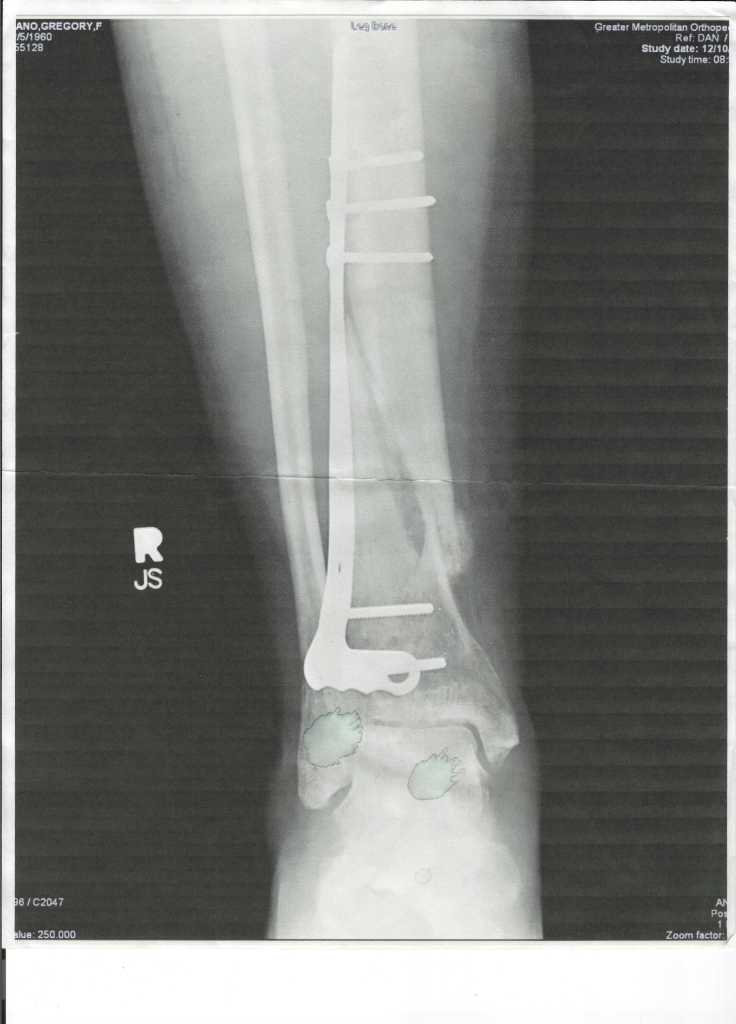

Greg has a BIG scar on his calf. Several years ago he was riding through the woods on a dirt bike when his confidence and his abilities no longer matched and he crashed. Fortunately the guy he was riding with was able to call 9-11. The spiral fracture of his tibia resulted in surgery with pins and screws. He bemoans how well that scar healed, “Dudes need at least one good scar. They’re manly!”